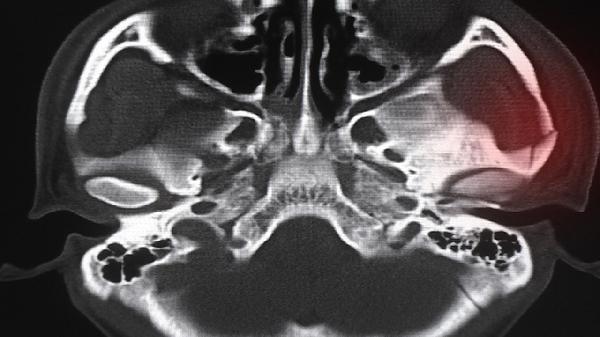

若骨骺线已完全闭合则难以自然增高,这种情况多出现在骨龄与实际年龄相符或超前的个体中。X线检查可明确骨骨骺闭合状态,内分泌检查能评估生长激素分泌功能。对于生长激素缺乏者,医生可能建议重组人生长激素注射液等治疗方案,但需严格评估适应证。不建议自行使用增高类保健品或采取牵引等非正规干预手段。